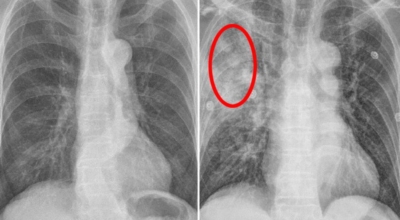

폐암은 폐에 생긴 악성 종양입니다. 폐 자체에 나타나는 원발성 폐암과 다른 장기에서 전이되어 온 전이성 폐암이 있습니다. 전 세계적으로 해마다 130만 명이나 되는 사람들이 폐암으로 사망하는데 이는 암에 의하여 사망하는 것 중에 가장 높은 비중을 차지하고 있습니다.

폐암 초기증상